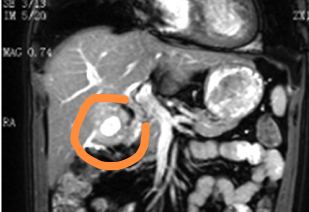

MRI 診斷膽囊腺肌癥 1 例

患者,男,56歲。主訴:右上腹疼痛20余天,伴乏力、怨油、食欲減退。外院超聲檢查提示膽囊占位,體查右上腹輕壓痛,其他無(wú)明顯陽(yáng)性體征。MRI顯示膽囊壁不規(guī)則增厚,伴水腫,增厚囊壁間可見(jiàn)多個(gè)大小不等類(lèi)圓形亮點(diǎn),約3~10mm,內(nèi)壁尚光滑,最厚達(dá)13mm,增強(qiáng)呈漸進(jìn)性強(qiáng)化,見(jiàn)圖1~5。行膽囊切除術(shù)后,送病理檢查回示膽囊腺肌增生癥彌漫型。膽囊腺肌癥MRI表現(xiàn):膽囊壁增厚,膽囊增大,囊壁可局限性、節(jié)段性或彌漫性增厚(厚度可大于10mm)、囊壁可見(jiàn)散在小點(diǎn)狀含液小憩室,以T2顯示最佳,有一定特異性,囊壁多平整、光滑,有時(shí)羅-阿氏竇內(nèi)可含有膽汁、膽固醇沉積或小結(jié)石而表現(xiàn)為信號(hào)不均質(zhì);增強(qiáng)掃描增厚膽囊壁表現(xiàn)為漸進(jìn)性明顯均勻強(qiáng)化。MRI見(jiàn)到擴(kuò)大的羅-阿氏竇有助于膽囊腺肌癥的診斷。脂肪餐試驗(yàn)可見(jiàn)膽囊收縮亢進(jìn),有助于診斷。本文選自:宋義光,MRI診斷膽囊腺肌癥1例原文鏈接地址:MRI診斷膽囊腺肌癥1例-中國(guó)知網(wǎng)(cnki.net)